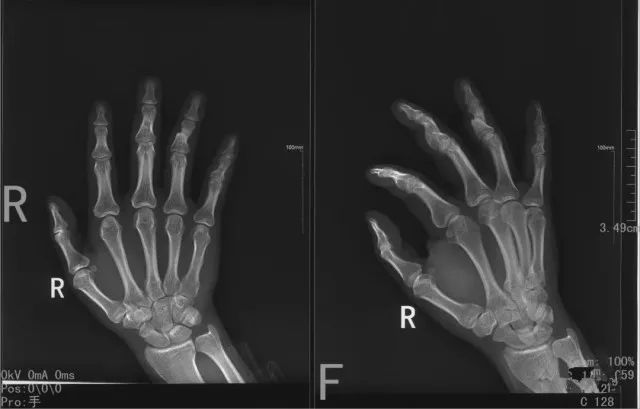

1、该“碰瓷”诈骗团伙中的“伤者”,自行制造其手指骨折,并在伤情恢复期间,频繁伪造交通事故,实施“碰瓷”诈骗,其作案手段隐蔽、误导性强。